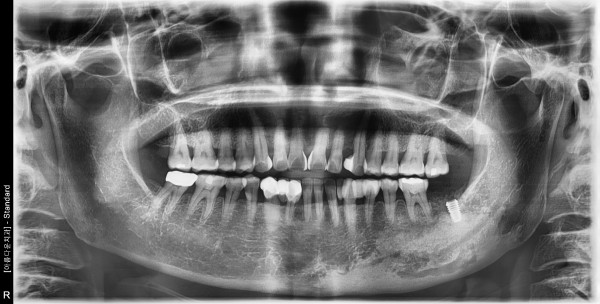

57세여자환자 / 하악좌측구치부발치후 뼈이식및 임플란트식립